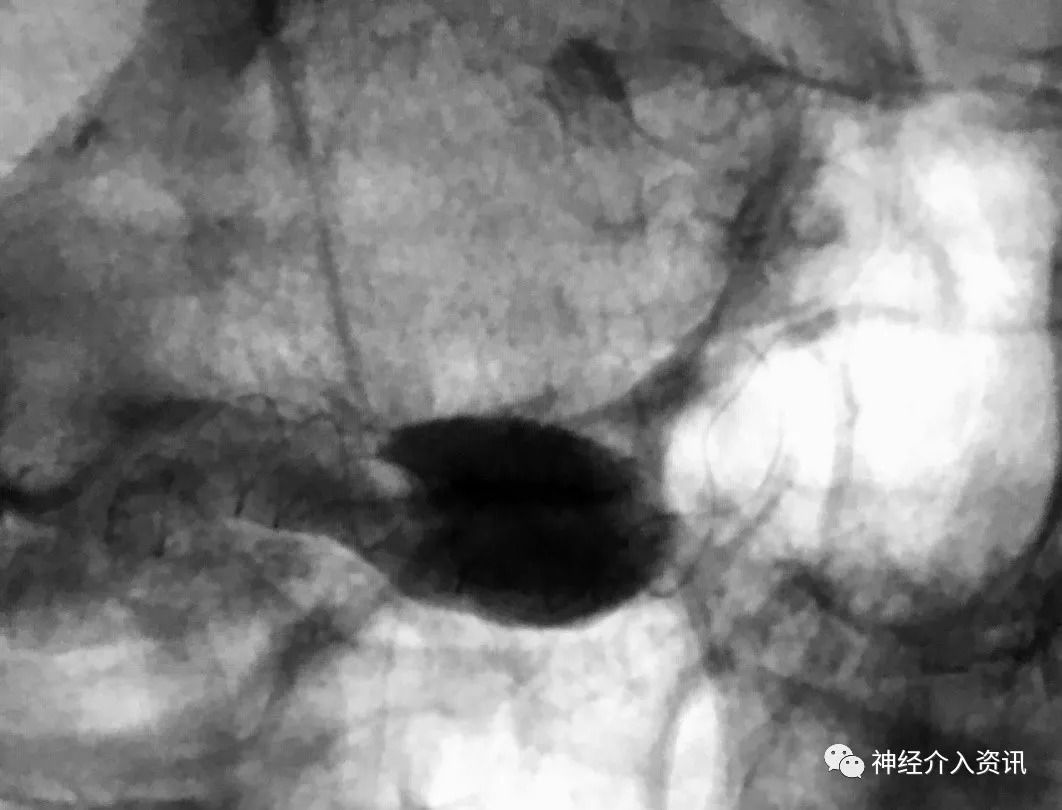

图3:血管重建装置释放后行血管内造影,造影剂进入动脉瘤的血流方式明显改变,缓慢充盈瘤体,瘤体充盈体积减小,静脉晚期可见造影剂滞留非常明显。